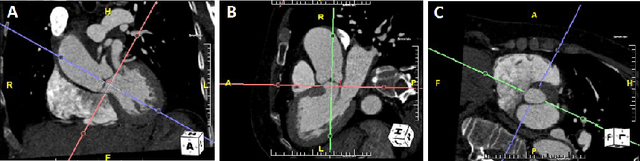

Abstract:Objective: Surveillance imaging of chronic aortic diseases, such as dissections, relies on obtaining and comparing cross-sectional diameter measurements at predefined aortic landmarks, over time. Due to a lack of robust tools, the orientation of the cross-sectional planes is defined manually by highly trained operators. We show how manual annotations routinely collected in a clinic can be efficiently used to ease this task, despite the presence of a non-negligible interoperator variability in the measurements. Impact: Ill-posed but repetitive imaging tasks can be eased or automated by leveraging imperfect, retrospective clinical annotations. Methodology: In this work, we combine convolutional neural networks and uncertainty quantification methods to predict the orientation of such cross-sectional planes. We use clinical data randomly processed by 11 operators for training, and test on a smaller set processed by 3 independent operators to assess interoperator variability. Results: Our analysis shows that manual selection of cross-sectional planes is characterized by 95% limits of agreement (LOA) of $10.6^\circ$ and $21.4^\circ$ per angle. Our method showed to decrease static error by $3.57^\circ$ ($40.2$%) and $4.11^\circ$ ($32.8$%) against state of the art and LOA by $5.4^\circ$ ($49.0$%) and $16.0^\circ$ ($74.6$%) against manual processing. Conclusion: This suggests that pre-existing annotations can be an inexpensive resource in clinics to ease ill-posed and repetitive tasks like cross-section extraction for surveillance of aortic dissections.